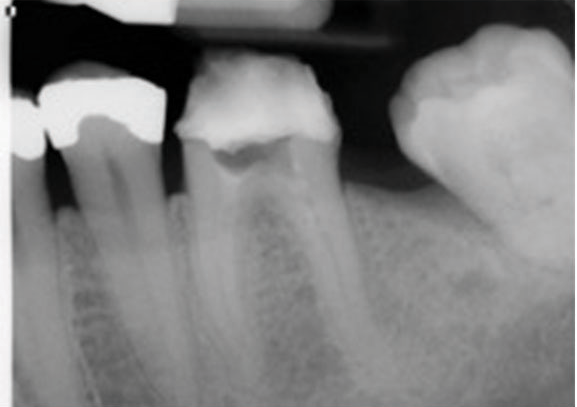

(7.) One-year follow-up periapical and bitewing radiographs demonstrating the absence of apical pathosis or furcal pathosis at the site of

the perforation.

Figure 7

(8.) One-year follow-up periapical and bitewing radiographs demonstrating the absence of apical pathosis or furcal pathosis at the site of

Figure 8